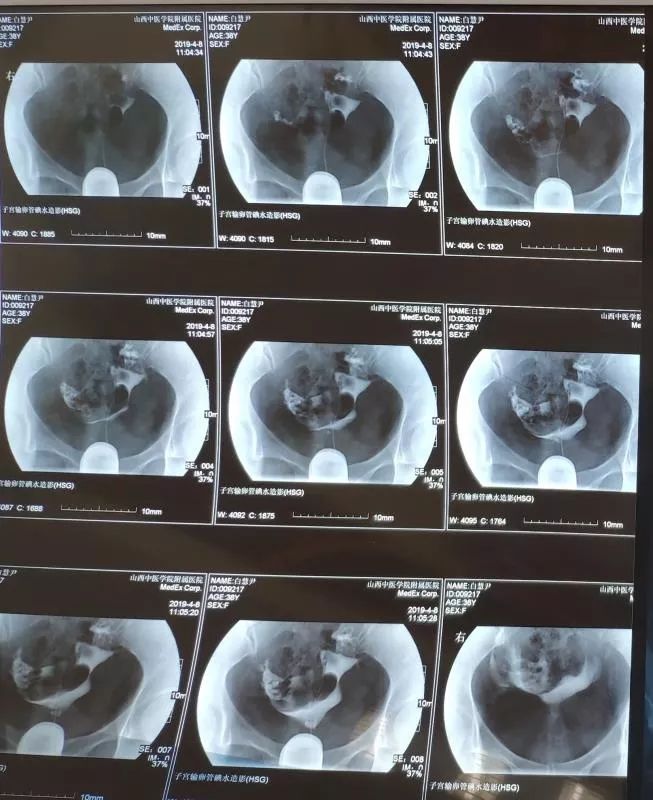

白女士,3月前因不孕症查子宫输卵管造影:输卵管双侧梗阻,少量造影剂弥散(即双侧输卵管不通)如下图:

在不孕不育科中药内服+外治(中药保留灌肠+热敷)治疗三个月后,复查子宫输卵管造影:双侧输卵管通而不畅,造影剂弥散均匀,该患者经治疗后输卵管由不通转为通畅。